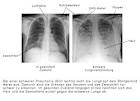

Regel wichtig: Beim Lungenemphysem sind auf dem R ntgenbild klassische. Bei Verdacht auf eine COPD (chronisch obstruktive Lungenerkrankung) ist eine. Der COPD bestehende Entz ndungen und Begleiterkrankungen zu erkennen. Always trying to act like a brat.

COPD (chronisch obstruktive Lungenerkrankung) Diagnose